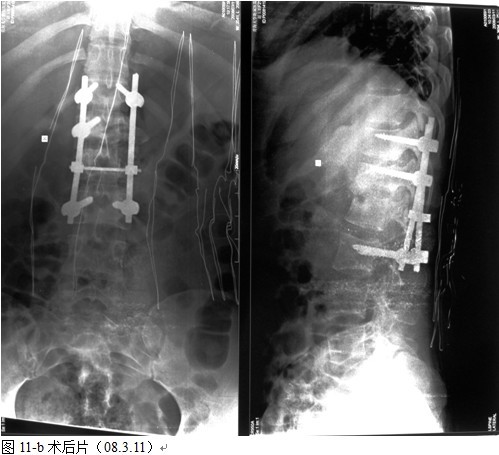

本组手术用时间3~4h , 平均3.5h 。术中出血300~500ml , 平均约350ml 。术后症状完全缓解,无神经功能障碍加重等并发症,1例营养差的老年患者伤口出现窦道,1例因肝功能差,术后未口服抗痨药,伤口出现窦道,经换药后二期愈合,其余病例伤口均一期愈合。马尾神经受损的患者术后基本恢复正常。术后一周后凸角平均 5.4°后凸畸形平均矫正90%以上, 最终后凸角平均8.3°,后凸角度平均丢失4.2°。随访3个月有87%(40/46)有骨痂形成,6个月91.3%(42/46)明显骨性愈合(见图),其余4例9-12个月内愈合,随访时间3-32个月,平均11个月,46例患者中2例在术后2个月和3个月时背部形成脓肿,换药后治愈。2例出院1月后并发结核性脑膜炎,治疗后好转。1例因椎弓根钉偏外,刺激神经根,5个月后从侧方脱出,疼痛加重,因前后路植骨完全愈合,取出后症状完全缓解。

中国学者金大地[22]等采用一期前路病灶清除植骨前路钢板固定治疗腰椎结核,平均18°的后凸畸形得以矫正,Mukhtar[23] AM等采用前路病灶清除植骨分期或同期后路固定治疗腰椎结核22例,术后后凸畸形矫正度数平均为27°。从我们的随访结果看,术后后凸畸形平均矫正度数为26.9°,后凸畸形平均矫正90%以上, 6个月-49个月后随访,后凸角度平均丢失4.2°。本术式也适用于结核所引起的弹性差的后凸畸形,对于病灶纤维化或骨化的非弹性后凸畸形,后路固定后,先行前路病灶、纤维化或骨化切除、松解,逐步刮除病灶、逐步撑开,达到畸形矫正和植骨的目的。